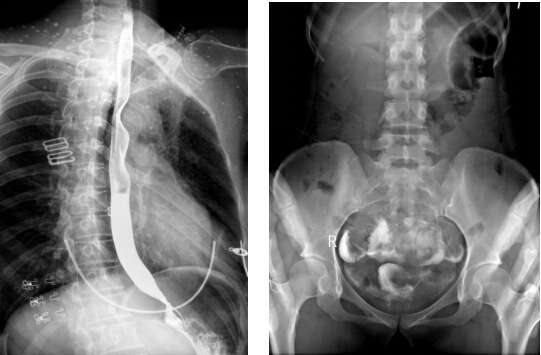

實(shí)時(shí)成像在動(dòng)態(tài)DR點(diǎn)片中,是一個(gè)硬性指標(biāo)。我們知道目前組合型的胃腸機(jī)也能夠?qū)崿F(xiàn)900萬(wàn)像素的點(diǎn)片影像輸出,但是有一個(gè)非常核心的問(wèn)題,那就是成像時(shí)間??梢韵胂笠幌?,一個(gè)患者在做腎盂造影,在可視化條件下觀察到腎臟某處有疑似病灶,此時(shí)進(jìn)行點(diǎn)片。

如果是組合式胃腸機(jī)進(jìn)行點(diǎn)片,需要通過(guò)電機(jī)將平板探測(cè)器傳送至指定位置,這個(gè)過(guò)程需要2-8S的時(shí)間,很容易錯(cuò)過(guò)病灶部位;如果是動(dòng)態(tài)DR,其能夠毫秒級(jí)時(shí)間內(nèi)進(jìn)行動(dòng)靜態(tài)影像切換,實(shí)時(shí)點(diǎn)片,就能夠很好地把握到影像的瞬間。